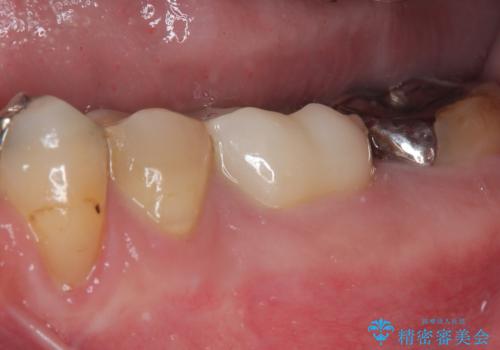

大臼歯の治療後に海外赴任され、数年ぶりに帰国されました。

奥歯に痛みがあるとのことで診察を行ったところ、海外(アメリカ)にて処置をした手前の歯が既に失活していることが分かりました。なお、治療を行った大臼歯はレントゲン写真上の治癒が認められました。

症状のあった歯に対しても根管治療を行い、同様に補綴治療を行いました。